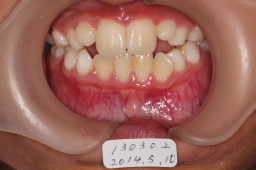

2013年03月02日 初診

前歯反対咬合

噛み合わせの高さをあげて、切歯斜面板で交叉咬合の改善を図る。骨格性の反対咬合

2014年05月10日

反対咬合は改善しているが、上顎切歯がはえる空間がないので、上顎歯列の拡大が必要。